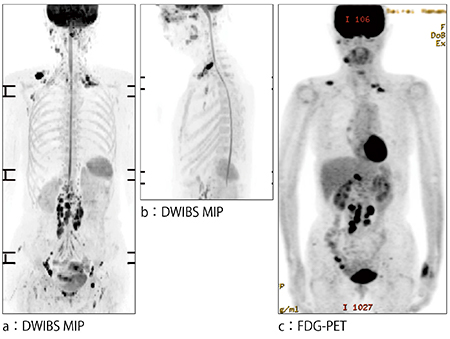

症例1:悪性リンパ腫

稼働間もない時点ですでに,3T装置と遜色ないパフォーマンスを発揮し,多くのメリットをもたらしているProdiva 1.5T CXであるが,聖隷三方原病院では,今後その能力を十分に生かせるよう,検査枠などの見直しなども検討している。高橋医長は,「セッティングを含めた検査スループットが良いので,骨転移症例の探索などに全身body DWIを積極的に使用できます。全身body DWIは,血液内科をはじめ,悪性腫瘍を扱う診療科の医師からも有用性が認められており,今後は検査枠を設けて施行していくことを検討しています」と述べる。高橋医長は,例えば悪性リンパ腫において,まずFDG-PET検査できちんと診断した上で,フォローアップを全身body DWIでも行うことで,その後のFDG-PET検査を減らすことも可能になると考えている。心臓MRIについても,現時点でもまったく問題なく撮像できているが,今後のバージョンアップでT1マッピングが可能となる予定で,よりいっそう有用な検査になることに期待している。